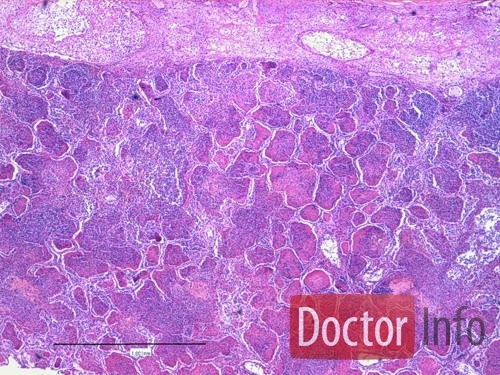

Этот вид пневмонии характеризуется поражением одной доли лёгкого, целого лёгкого или даже обоих лёгких. Чем больше объём поражения — тем тяжелее протекает процесс. Вызывается крупозная пневмония пневмококком. Кроме повреждения ткани легкого бактерия, выделяя токсичные для человека вещества, действует на весь организм – сильно повышается температура, появляется озноб.